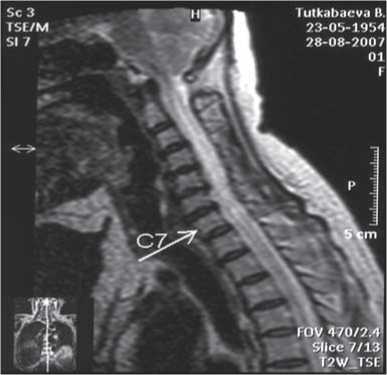

Эффективность лечения воспалительных заболеваний мозга представлена на примере лечения туберкулезного менингита (рис. 1), сирингомиелии (рис. 2, 3), перинатальной энцефалопатии и гидроцефалии (рис. 4), нейропатии лицевого нерва (рис. 5, 6) [12-15, 17].

Рис. 2. МРТ головного мозга и шейно-грудного отделов спинного мозга. Больная К., 53 года. Диагноз — сирингомиелия, шейная форма. Просматривается сирингомиелитическая полость на уровне 1 и 2 сегментов спинного мозга. Исследование выполнено до проведения лимфотропной терапии.

Рис. 3. МРТ C1—Th4сегментов спинного мозга спустя 3,5 месяца от начала лечения той же больной. Проведено 2 курса непрямой лимфостимуляции. На уровне 1 и 2 сегментов спинного мозга сирингомиелитическая полость не просматривается.